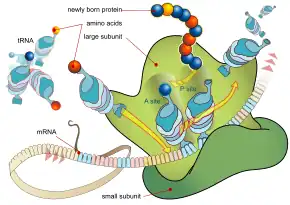

As a protein synthesis inhibitor, linezolid works by suppressing bacterial protein production.[8] This either stops growth or results in bacterial death.[1] Although many antibiotics work this way, the exact mechanism of action of linezolid appears to be unique in that it blocks the initiation of protein production, rather than one of the later steps.[8] As of 2014, bacterial resistance to linezolid has remained low.[9] Linezolid is a member of the oxazolidinone class of medications.[1]

Linezolid, like other oxazolidinones, is a bacterial protein synthesis inhibitor and a weak, non-selective, reversible monoamine oxidase inhibitor.[3][99] As a protein synthesis inhibitor, linezolid stops the growth and reproduction of bacteria by disrupting translation of messenger RNA (mRNA) into proteins in bacterial ribosomes.[3] Linezolid inhibits translation at the first step of protein synthesis, initiation,[3][100] unlike most other protein synthesis inhibitors, which inhibit elongation.[8][60] It does so by preventing the formation of the initiation complex, composed of the 30S and 50S subunits of the ribosome, tRNA, and mRNA. Linezolid binds to the 23S portion of the 50S subunit (the center of peptidyl transferase activity),[3][100] close to the binding sites of chloramphenicol, lincomycin, and other antibiotics. Due to this unique mechanism of action, cross-resistance between linezolid and other protein synthesis inhibitors is highly infrequent or nonexistent.[21][52]

In 2008, the crystal structure of linezolid bound to the 50S subunit of a ribosome from the archaean Haloarcula marismortui was elucidated by a team of scientists from Yale University and deposited in the Protein Data Bank.[101] Another team in 2008 determined the structure of linezolid bound to a 50S subunit of Deinococcus radiodurans. The authors proposed a refined model for the mechanism of action of oxazolidinones, finding that linezolid occupies the A site of the 50S ribosomal subunit, inducing a conformational change that prevents tRNA from entering the site and ultimately forcing tRNA to separate from the ribosome.[102]